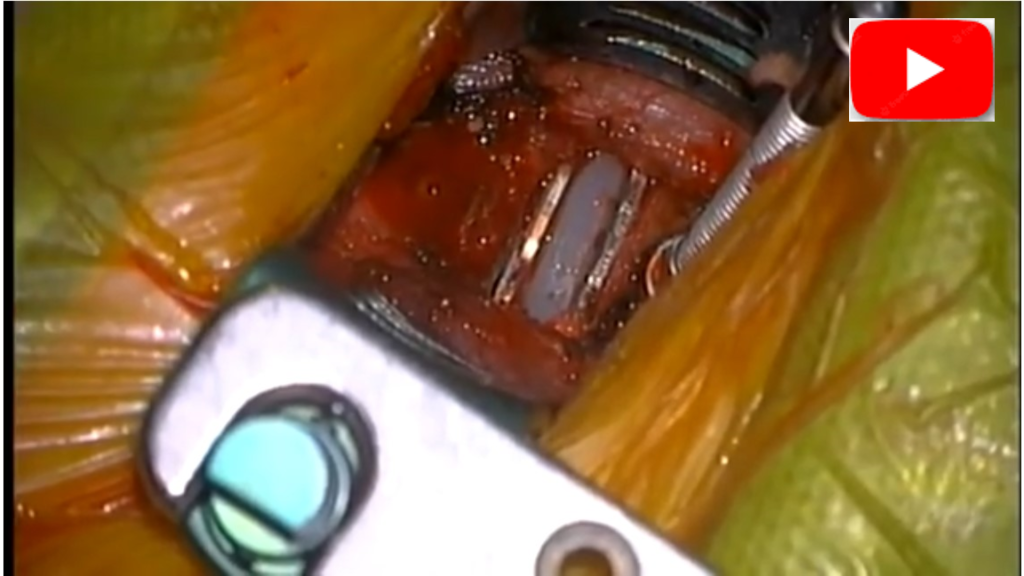

O objetivo da cirurgia é descomprimir a medula e estabilizar a coluna. A via de acesso anterior (pela frente do pescoço) é a mais comum para compressões de 1 a 2 níveis. Neste caso realizamos os seguintes procedimentos nos níveis de ac3-C4 e C4-C5:

1. Microdiscectomia Anterior: Utilizando um microscópio cirúrgico, o disco intervertebral comprometido é removido com precisão, aliviando a pressão sobre a medula e as raízes nervosas.

2. Artrodese com Cage Stand-Alone: No espaço do disco removido, é implantado um “cage” (um espaçador). O modelo “stand-alone” é projetado para ser estável por si só, muitas vezes com parafusos bloqueados em suas placas laterais, dispensando a necessidade de uma placa anterior adicional. Ele mantém a altura do disco, restabelece o alinhamento da coluna e promove a fusão óssea (artrodese) definitiva entre as vértebras.

Vantagens: Procedimento minimamente invasivo, descompressão eficaz, alta taxa de fusão óssea, recuperação mais rápida e menor dor pós-operatória comparado à via posterior.